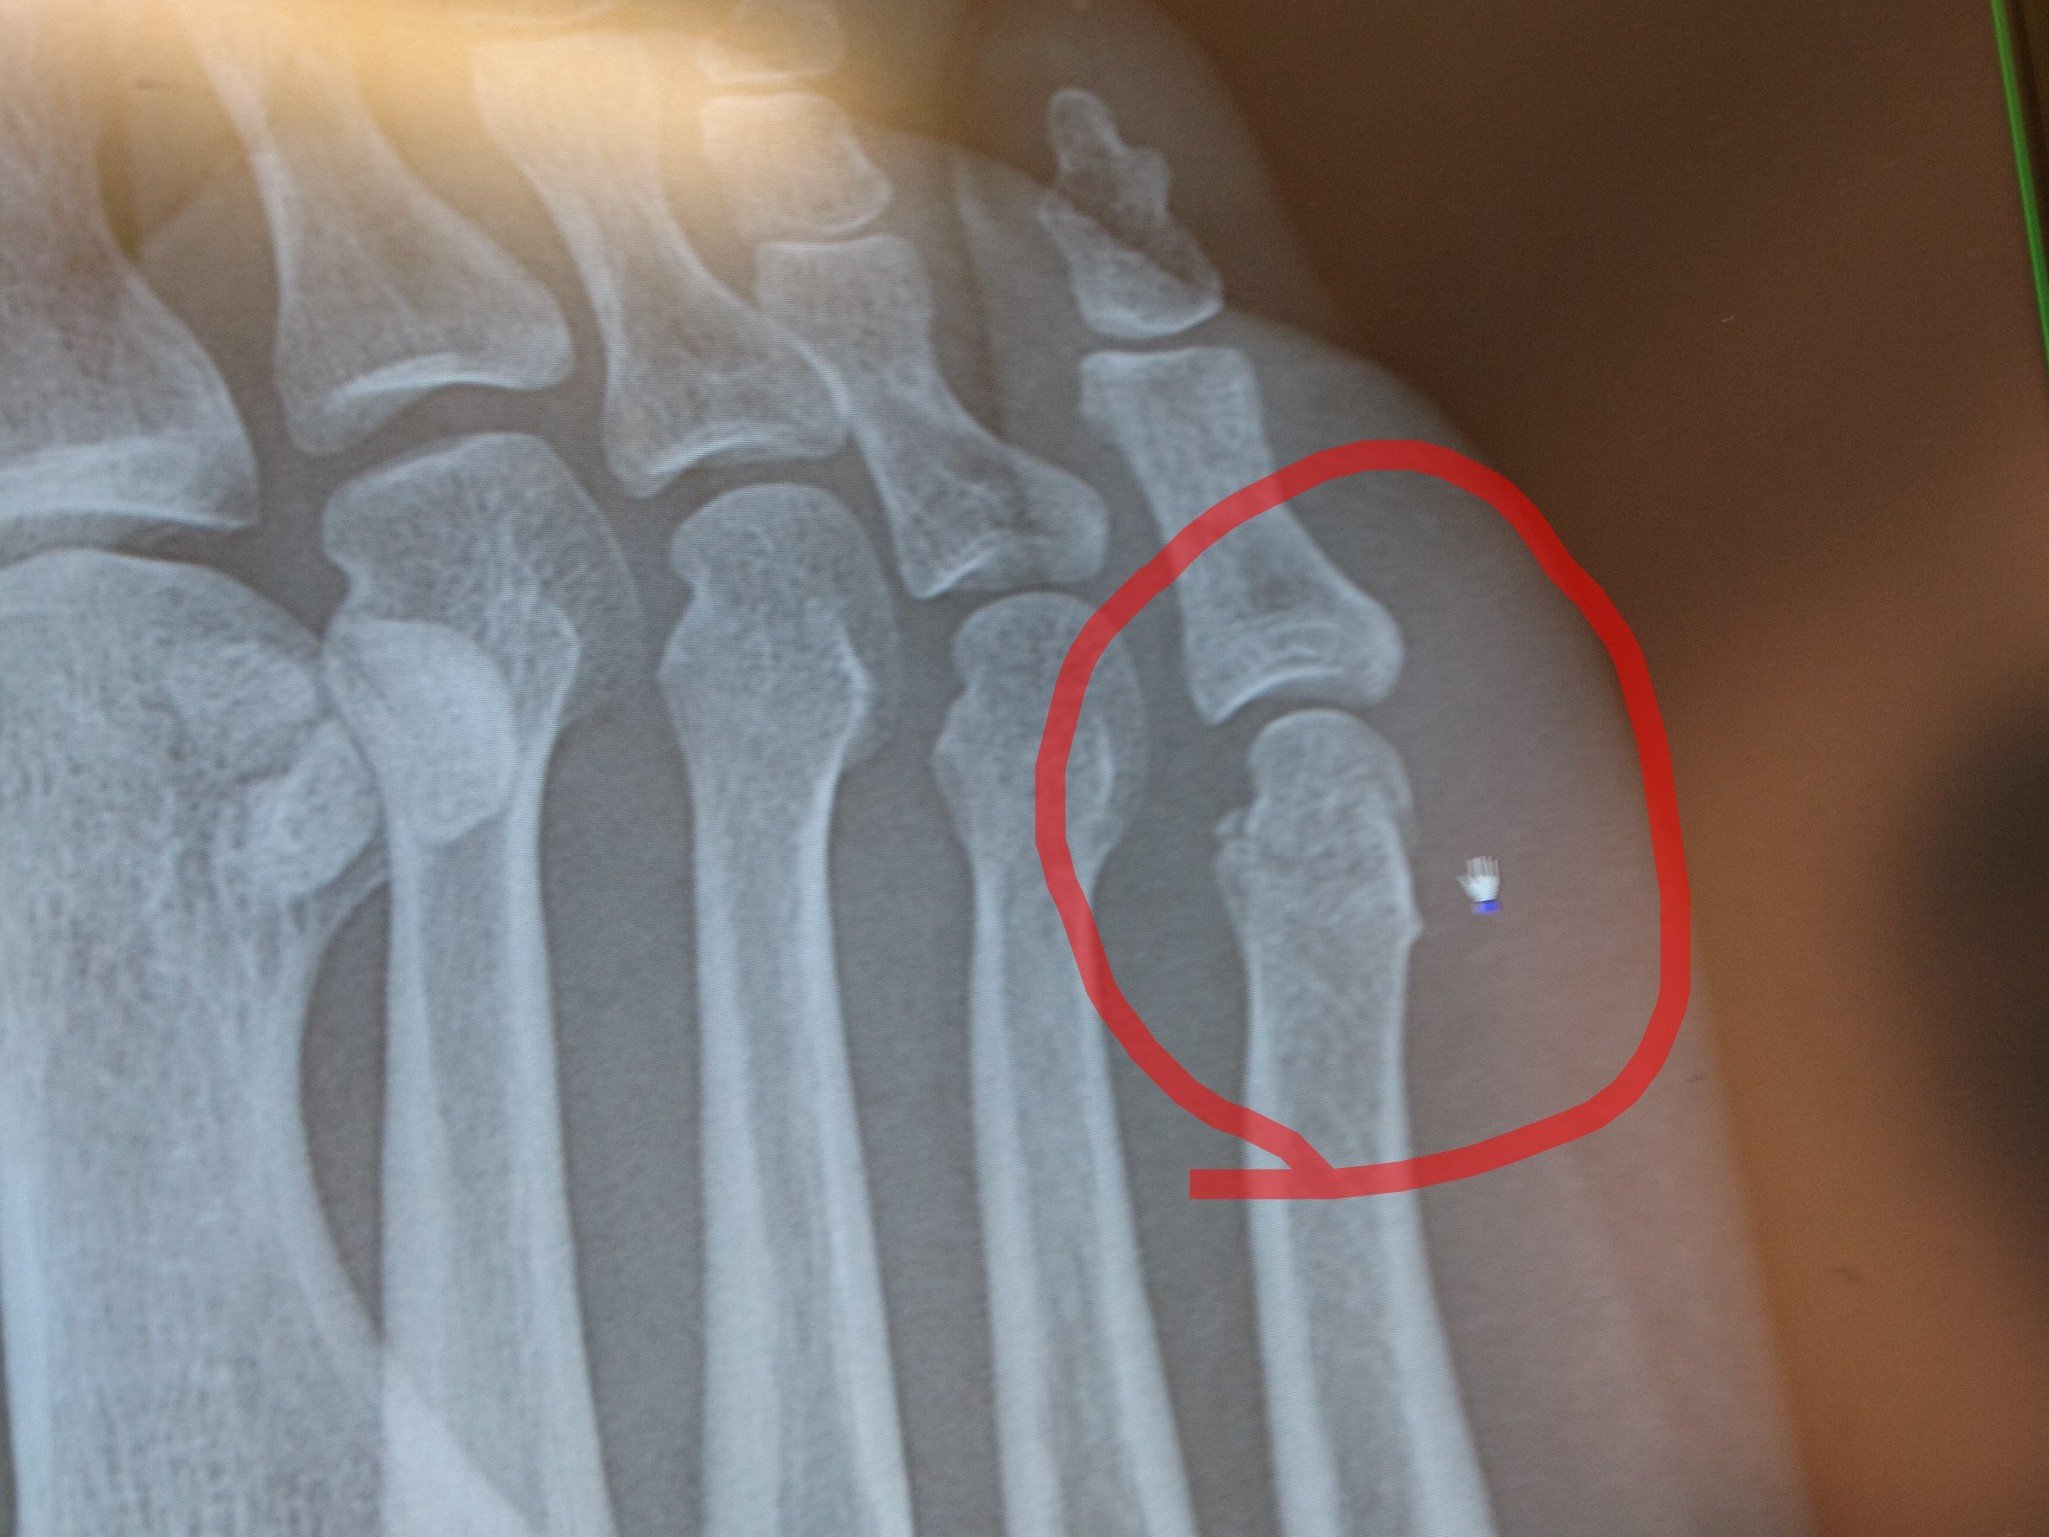

足舟状骨裂離骨折 これは有痛性外脛骨ではなく 骨折です 古東整形外科 リウマチ科